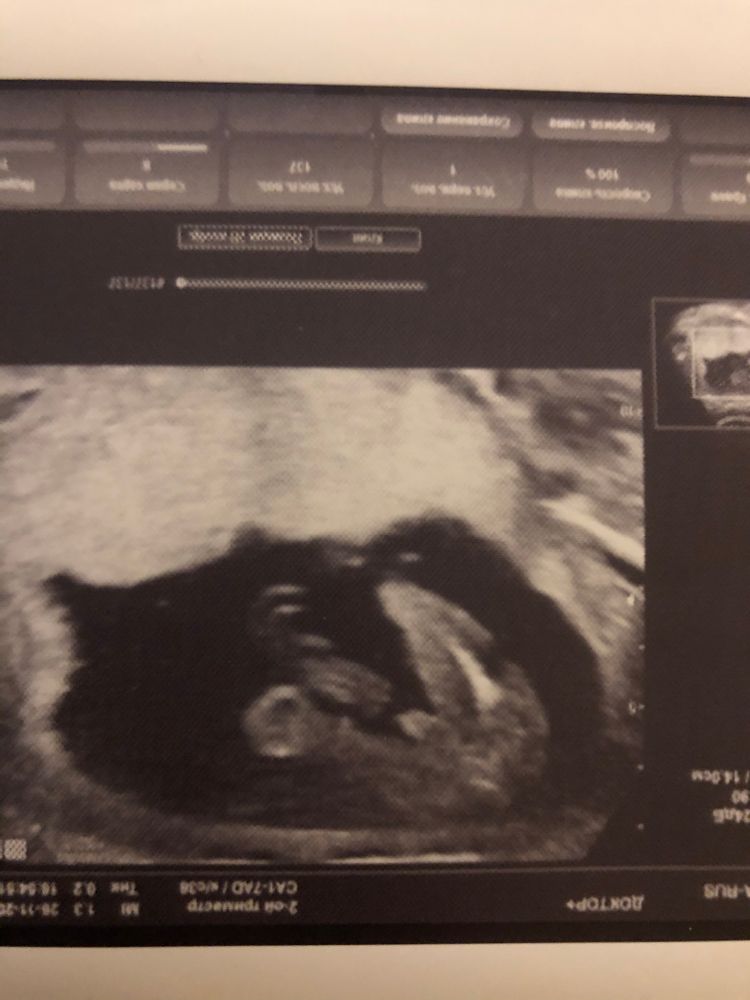

Пацан?

Сынок это.мне тоже такие пипеточки показыв и фотки тоже где то есть.а в этот раз вроде пирожок показали,но так боюсь разочароваться потому что настроилась уже вроде. вдруг спутали и хоботок спрятался.тоже так девочку хотели.будкм ждать родов😀🙏

Пацан)

Очень похоже на мальчугана, у нас похожее фото было😊 Поздрааляю🌹